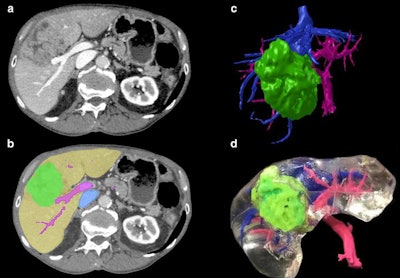

To see if 3D printing could help resolve this limitation, the researchers obtained CT scans from 19 patients with liver cancer who were scheduled for laparoscopic liver resection or radiofrequency ablation between April 2017 and December 2018.

The researchers segmented and processed the CT scans using open-source software (3D Slicer) and then created multicolor 3D-printed livers using polylactic acid filaments and a 3D printer (Ultimaker 2+, Ultimaker). The entire production sequence, from imaging to silicone casting, took roughly five days (Eur Radiol, November 26, 2019).

Examining the patient-specific models presented the surgical planning team, which included several surgeons and radiologists, with a precise 3D view of the liver tumors in relation to liver anatomy, according to the researchers. During presurgical planning, examining the models helped convince the team to change its previously established surgical approach (based on CT scans alone) for 26.3% of the cases. They considered all but one of the altered approaches to be a major change.

The 3D-printed models helped the surgical team to determine not only the ideal resection line but also the extent to which liver tissue needed to be resected, the group noted. Despite not revealing any new malignancies, the 3D-printed models changed the surgical plan in more than a quarter of the cases, likely due to the improved understanding they offered concerning the spatial relationships between liver vasculature and lesions.